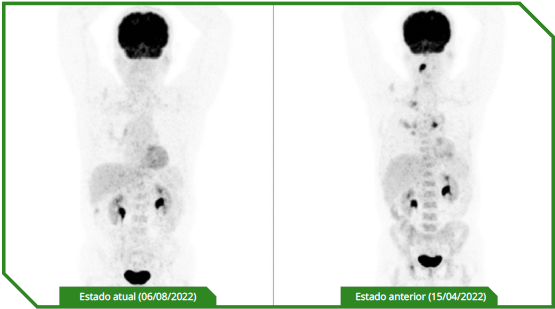

Paciente masculino de 65 anos, previamente sem comorbidades, diagnosticado com carcinoma espinocelular de língua, tratado inicialmente com cirurgia e radioterapia adjuvante, evoluindo precocemente com doença metastática pulmonar e óssea. No momento da avaliação oncológica, apresentava performance status comprometido e alta expressão de PD‑L1 (CPS 30). Optou-se por imunoterapia isolada em primeira linha, considerando perfil clínico e objetivo de redução de toxicidade, com acompanhamento longitudinal e intervenções locais conforme necessidade.